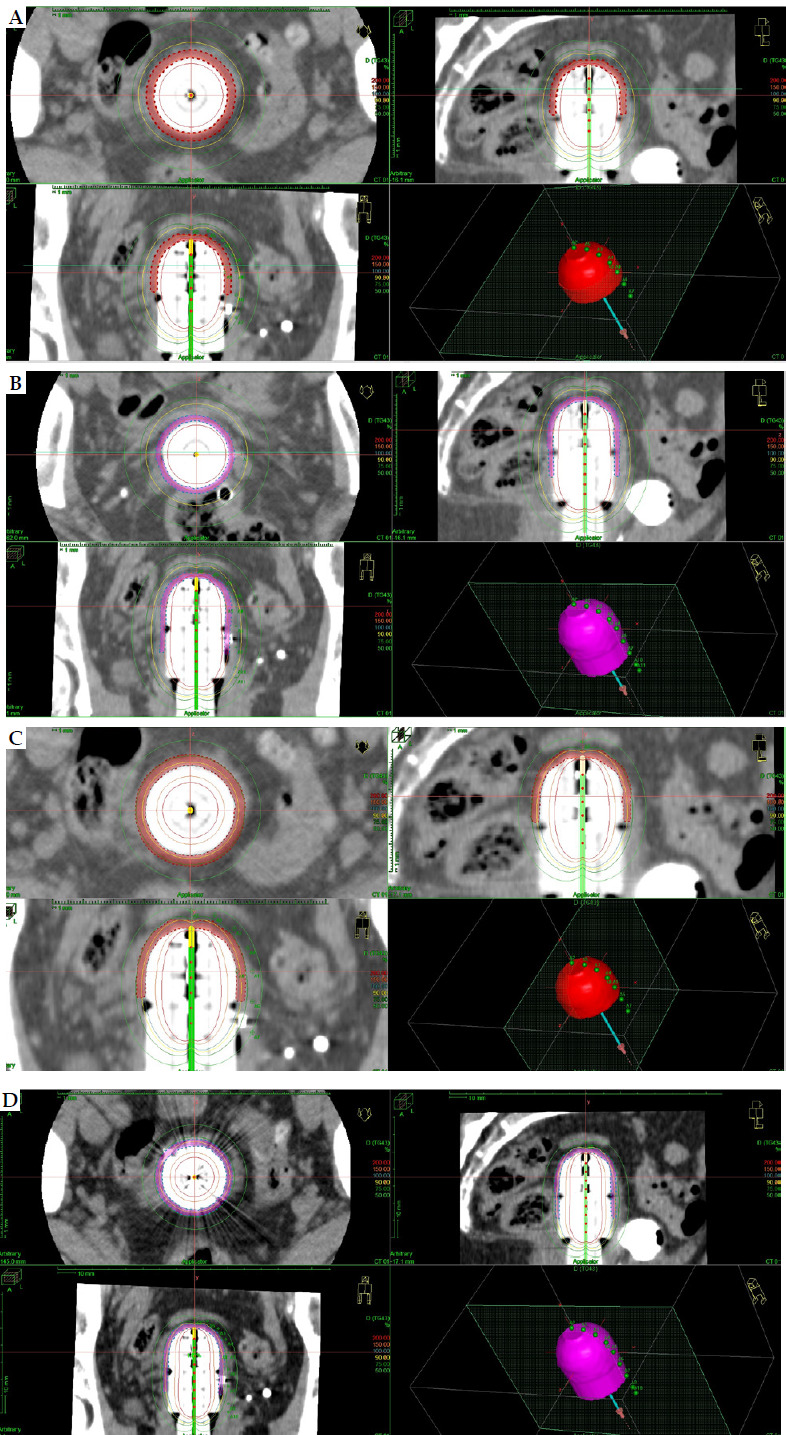

Material and methods: Three different computed tomography (CT) studies for vaginal cylinders of 3.5 cm, 3 cm, and 2.5 cm were performed. Clinical target volume (CTV) was delineated for 3 cm and 4 cm of vaginal length. Twelve schedules were analyzed obtaining overall vaginal surface dose (Gy) (EQD2 α/β = 10 and α/β = 3), overall D90 CTV (α/β = 10) (Gy), and overall D2cc (α/β = 3) for organs at risk (OARs), such as vagina, rectum, sigmoid, rectum, and bladder. Prescription at 5 mm from the applicator surface and at the surface were analyzed for each case.

Results: The overall vaginal surface dose and dose to CTV varied widely among the different schedules, and CTV delineation was necessary in case of surface prescription. The applicator diameter of 3.5 cm showed the best dosimetry results for vaginal surface dose. The overall D2cc OARs' doses changed in the different CT studies.

Abstract Image